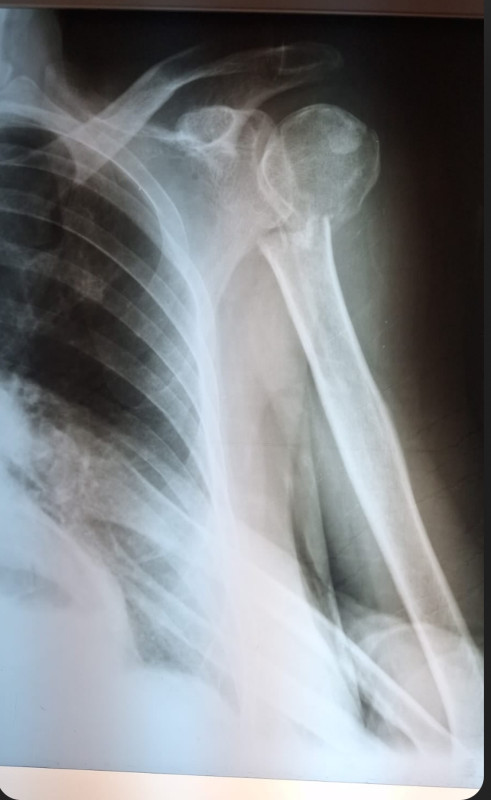

I urgently need shoulder replacement surgery after falling and badly breaking my arm at the joint. I don’t have insurance for this and let’s be honest, who’s got $11,000 just lying around? If I don’t have the surgery I’m facing the loss of use in that arm. I’m throwing out Hail Marys at this point because the pain is extraordinary and I am desperate to get this chapter done and over with. I’ve raised almost $4,000 so far but will need more for caregivers and travel and physical therapy. I am so grateful for the folks who have already donated to help me, and every little bit helps. I am forever grateful to them and would be so grateful to any other others who can help out. Thank you and much love.